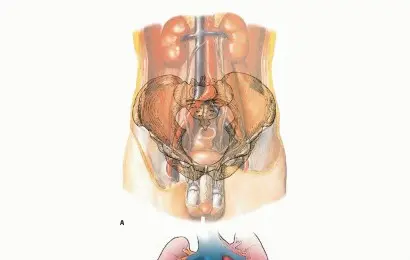

لفهم كيفية تأثير أورام العظام، من الضروري أولاً استعراض سريع لبنية العظم ووظيفته. العظام هي النسيج الأساسي الذي يشكل الهيكل العظمي لجسم الإنسان، وتلعب أدوارًا حيوية متعددة، بما في ذلك:

يتكون العظم من عدة أنواع من الأنسجة، أهمها:

عندما يتطور ورم في العظم، سواء كان حميدًا أو خبيثًا، فإنه يبدأ في النمو بشكل غير طبيعي داخل هذه البنى، مما يؤدي إلى: